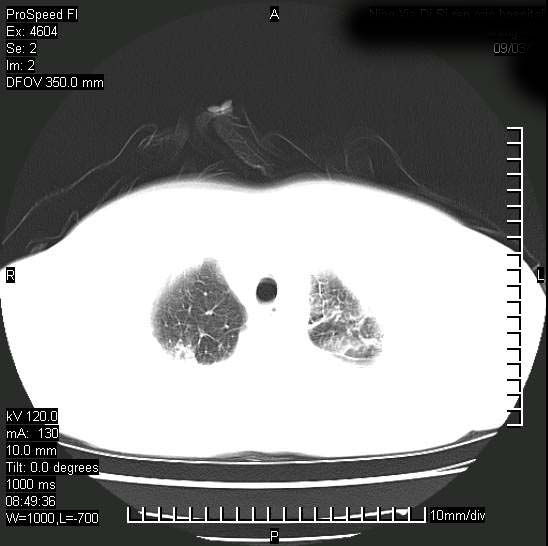

十几年前曾患肺结核,一周前突咳血约100ml,中性粒细胞稍高,诊断两上肺陈旧结核,下肺炎症,给予抗炎治疗,近几日晚上高热,39度,仍咳少量血,4天前ct及今天ct上传。

[face=黑体]8月30日[/face]

支持陈旧性肺结核并两下肺感染,两侧胸腔积液。

考虑1双肺tb灶;右下肺支气管壁增后,建议除外占位 3双侧胸腔积液,

短短几天内,病变范围明显增多扩大,以左侧明显,而且双侧出现胸水,还是考虑感染.

支持  结核ban感染,节段性肺不张,支气管内膜结核可能

继发性结核感染加重。左侧合并有支气管内膜结核。

无论是肿瘤还是炎症4天的时间都发展够快的,并且还在治疗中,如果说是左肺癌那么右肺的病变不好解释,本人更加倾向于炎症,左肺舌叶支气管被痰栓或血凝块堵塞,造成阻塞性肺炎。

1)两肺结核并感染。2)不排除左肺上叶中央型肺癌并阻塞性肺炎、肺不张可能;建议行纤支镜检查。3)右肺门及纵隔淋巴结肿大。4)双侧胸腔积液。